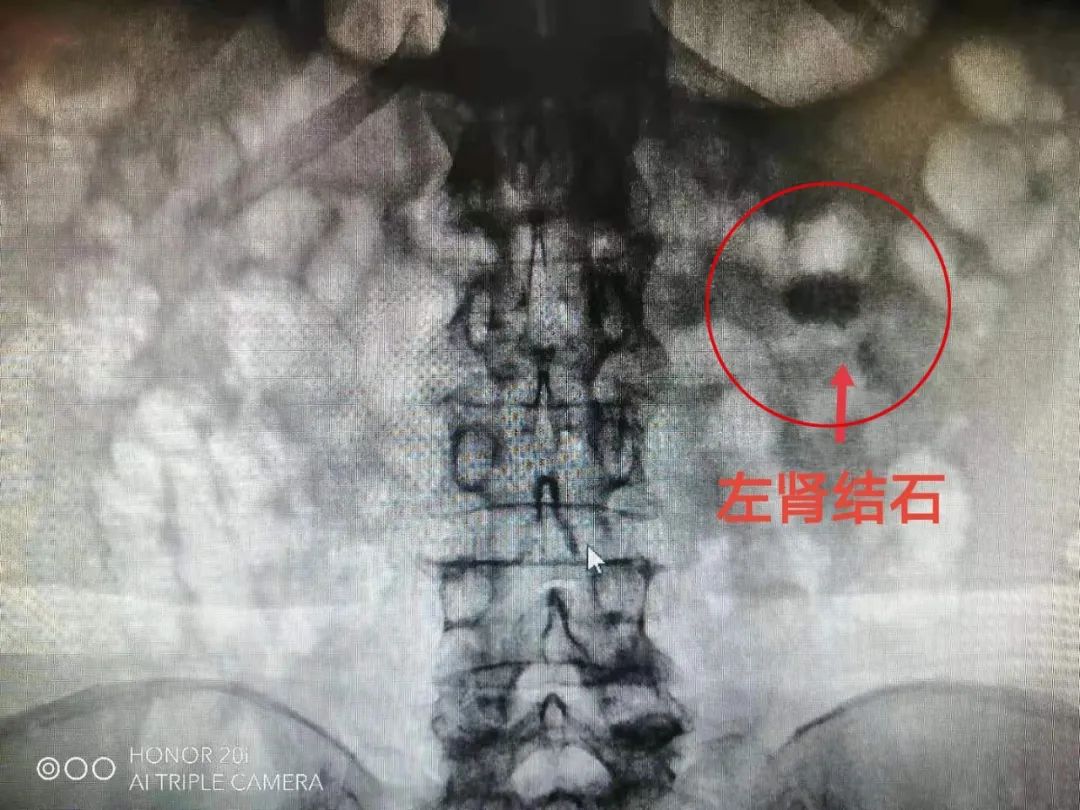

术前拍片,最大结石接近3cm吕夷松博士团队给黄阿姨进行了细致检查,并会诊讨论,诊断为左肾功能性孤立肾、左肾多发结石,结石较大,最大接近3cm。